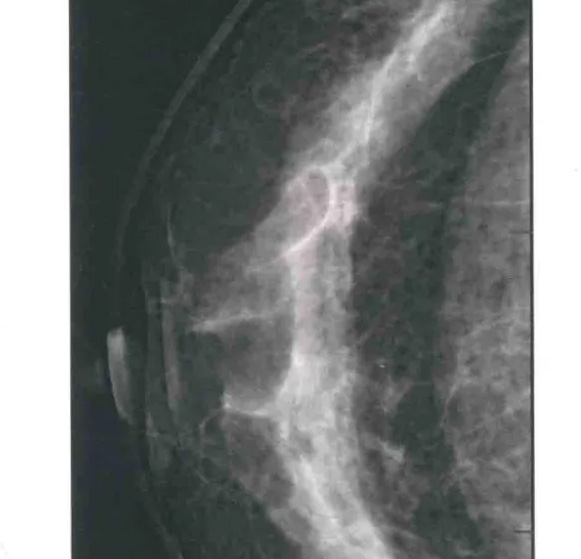

二、圖像顯示要求,含乳腺的基底部及內外側乳腺組織,需要顯示胸肌前緣或胸壁。頭尾位與內外斜位乳頭后線長度差≤1厘米;顯示實質后的乳腺組織,乳頭位于切線位,乳腺組織重疊;雙側乳腺頭尾位照片相對放置,則兩側乳腺呈球形;影像密度和對比度良好,能顯示0.1毫米細小鈣化,清晰沒有偽影異物、運動偽影和切割偽影等。